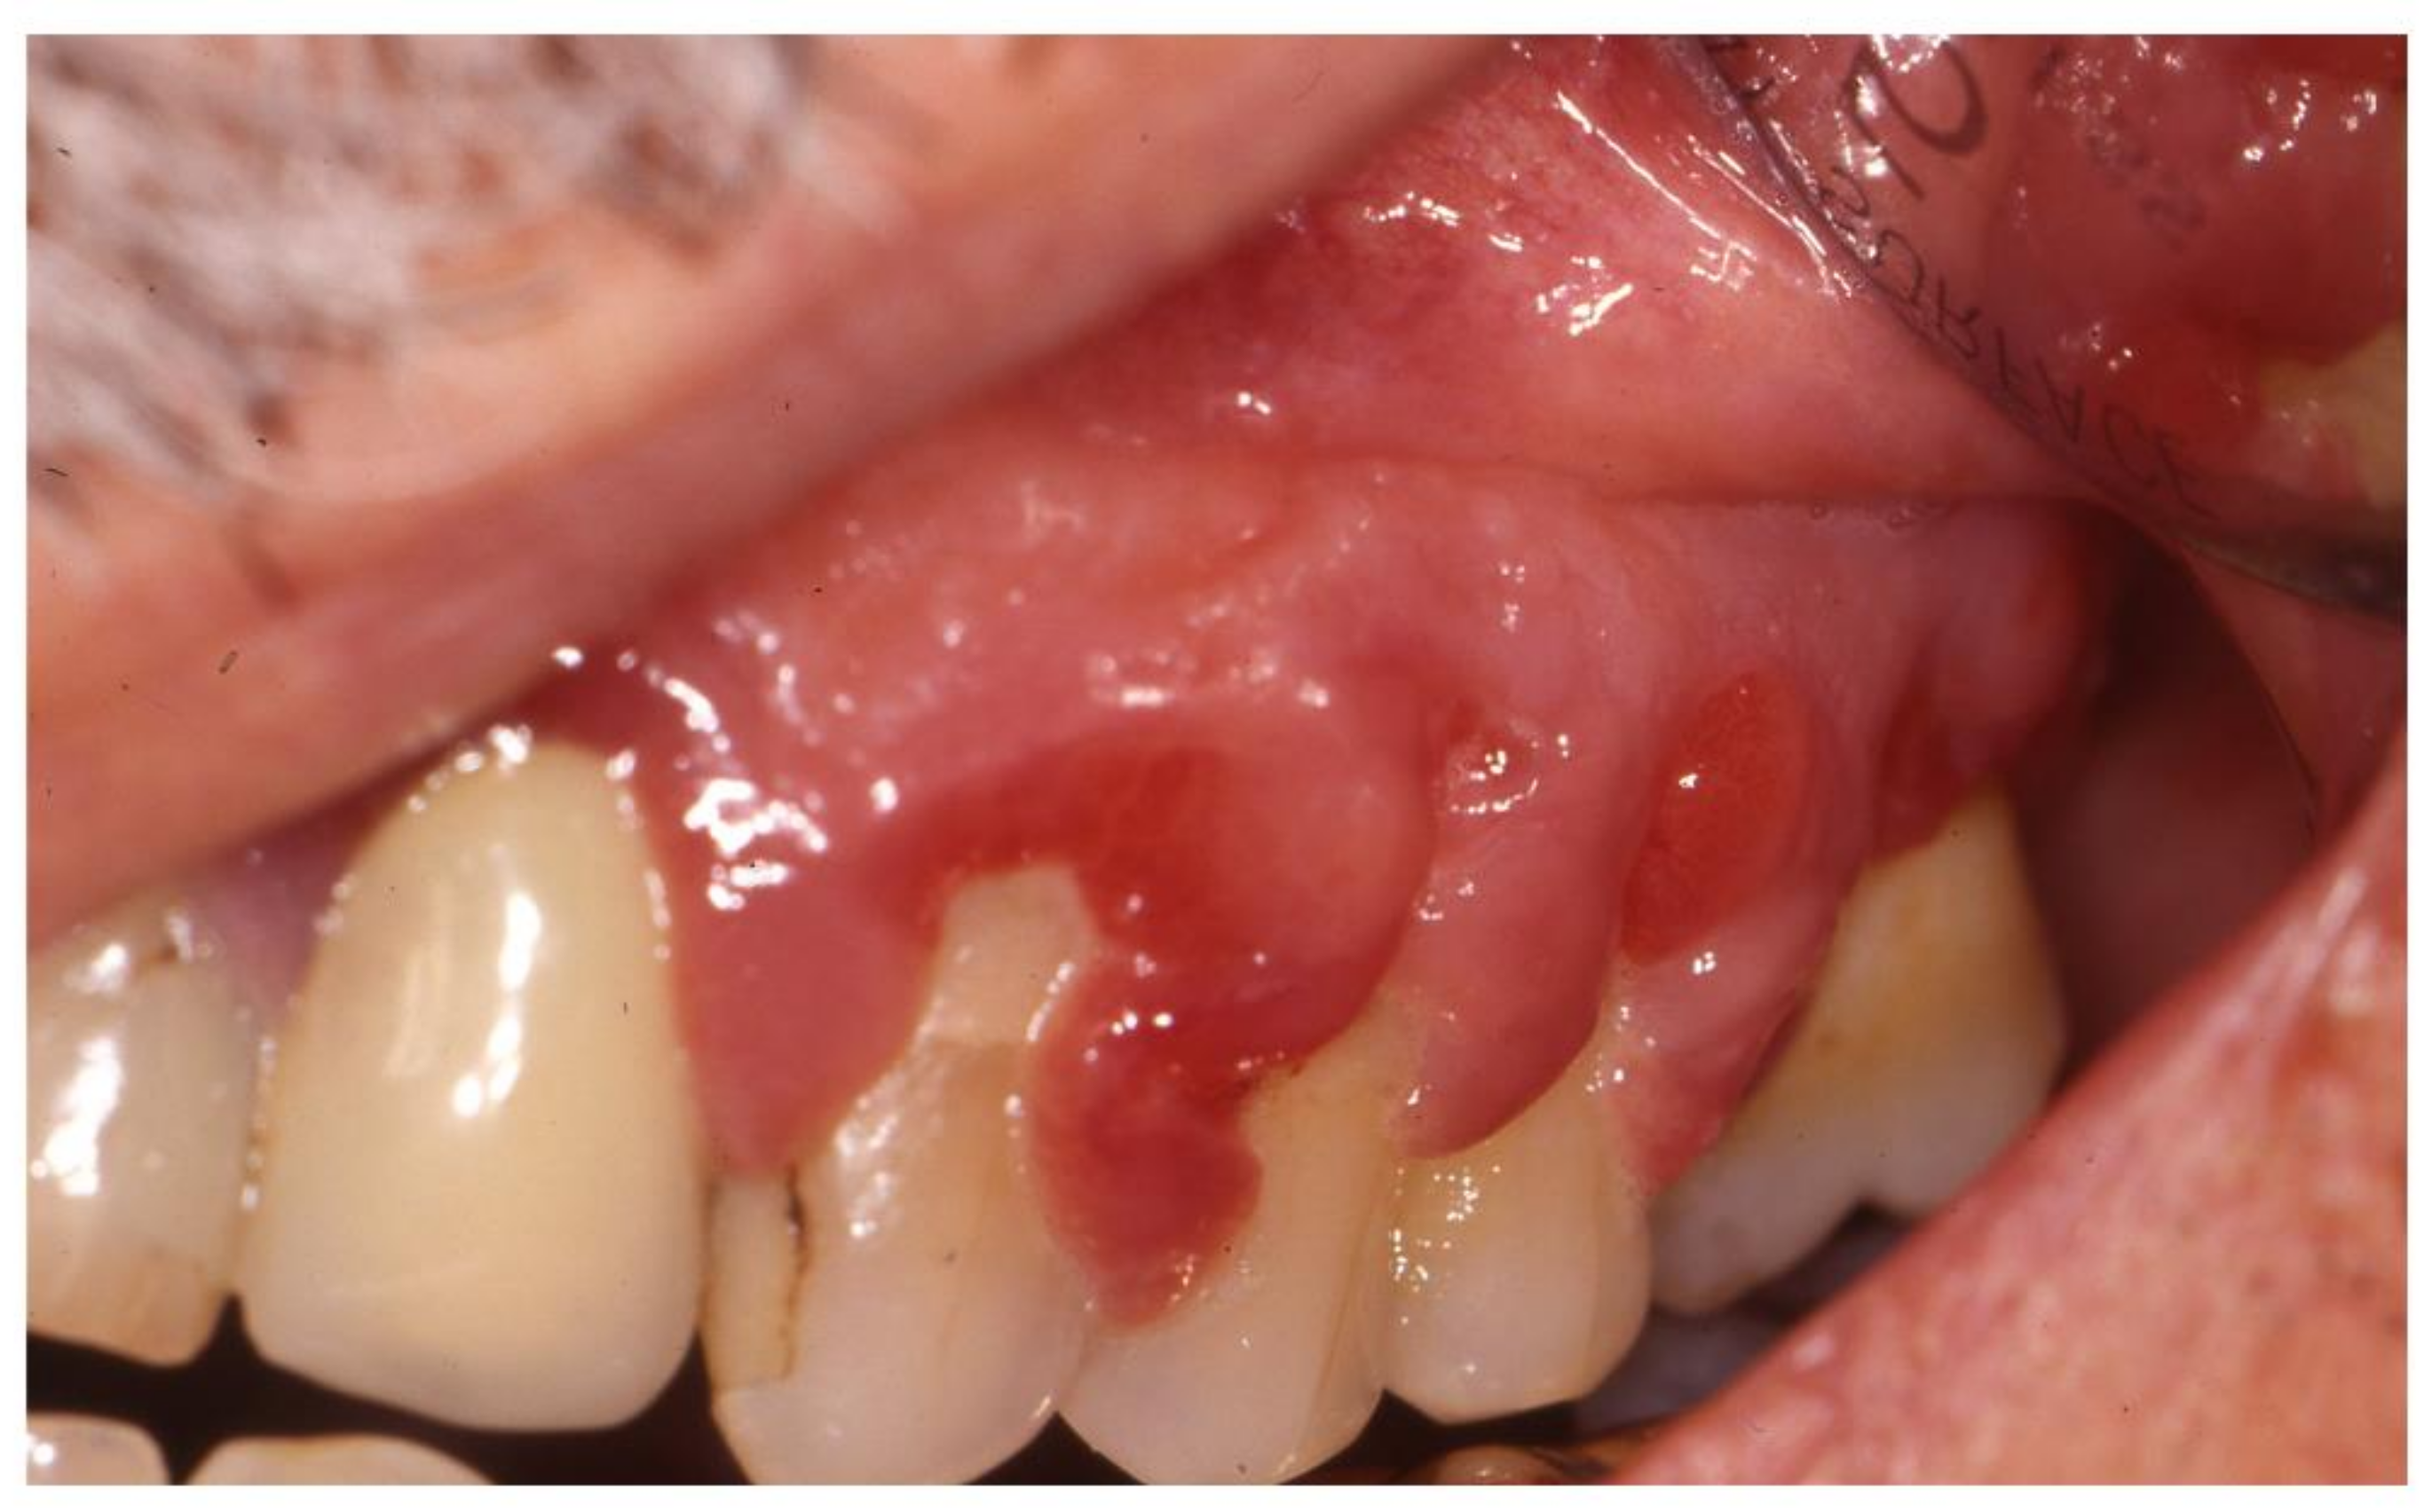

2.5. Gingival Overgrowth

- Ghiasi, M. Strawberry Gingivitis in Granulomatosis with Polyangiitis. N. Engl. J. Med. 2017, 377, 2073. [Google Scholar] [CrossRef]

- Hernandez, G.; Serrano, C.; Porras, L.; Lopez-Pintor, R.; Rubio, L.; Yanes, J. Strawberry-like gingival tumor as the first clinical sign of Wegener’s granulomatosis. J. Periodontol. 2008, 79, 1297–1303. [Google Scholar] [CrossRef]

| Granulomatosis with polyangiitis | Granulomatous vasculitis involving small arterial and venous vessels | cANCA (anti-PR3) | Strawberry-like gingivitis | [27,28] |